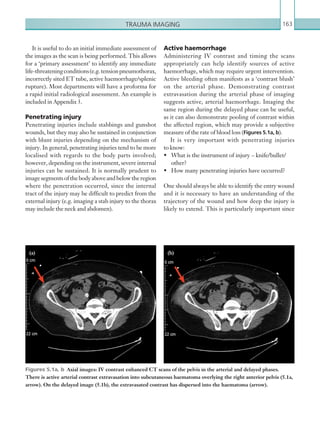

• 10.

Contentsvi Radiological findings54 Computed tomography54 Plainfilms56 Key points56 Report checklist56 References56 OESOPHAGEAL PERFORATION 57 Radiological investigations57 Radiological findings 58 Computed tomography 58 Fluoroscopy58 Plain films 59 Key points 59 Report checklist 59 Reference59 ACUTE APPENDICITIS 60 Radiological investigations 60 Radiological findings 60 Computed tomography 60 Ultrasound62 Key points 62 Report checklist 62 References62 ACUTE PANCREATITIS 64 Radiological investigations 64 Radiological findings 65 Computed tomography 65 Key points 67 Report checklist 67 References67 ACUTE DIVERTICULITIS 68 Radiological investigations 68 Radiological findings 68 Computed tomography 68 Key points 70 Report checklist 70 References70 ACUTE CHOLECYSTITIS 71 Radiological investigations 71 Radiological findings 71 Ultrasound71 Computed tomography 72 K22247_FM.indd 6 16/05/15 3:05 AM

• 11.

Contents vii Key points73 Report checklist 73 Reference73 EMPHYSEMATOUS PYELONEPHRITIS 74 Radiological investigations 74 Radiological findings 74 Computed tomography 74 Ultrasound76 Abdominal plain film imaging 76 Key points 76 Report checklist 77 References77 HYDRONEPHROSIS78 Radiological investigations 78 Radiological findings 78 Ultrasound78 Computed tomography 79 Key points 80 Report checklist 80 RENAL TRANSPLANT DYSFUNCTION 80 Radiological investigations 81 Radiological findings 81 Ultrasound81 Computed tomography 83 Key points 84 Report checklist 84 Reference84 LIVER TRANSPLANT DYSFUNCTION 85 Radiological investigations 85 Radiological findings 85 Ultrasound85 Computed tomography 87 Key points 87 Report checklist 87 References87 TUBO-OVARIAN ABSCESS 88 Radiological investigations 88 Radiological findings 88 Ultrasound88 Computed tomography 88 K22247_FM.indd 7 16/05/15 3:05 AM

• 12.

Contentsviii Key points 90 Reportchecklist 90 Reference90 OVARIAN TORSION 90 Radiological investigations 91 Radiological findings 91 Ultrasound91 Computed tomography 91 Key points 92 Report checklist 92 References92 TESTICULAR TORSION 93 Radiological investigations 93 Radiological findings 93 Ultrasound93 Key point 95 Report checklist 95 Reference95 CHAPTER 3: NEUROLOGY AND NON-TRAUMATIC SPINAL IMAGING 97 STROKE97 Radiological investigations 97 Radiological findings 98 Computed tomography 98 Magnetic resonance imaging 100 Key points 102 Report checklist 102 References102 CAROTID ARTERY DISSECTION 102 Radiological investigations 102 Radiological findings 103 Computed tomography 103 Magnetic resonance imaging 104 Key points 104 Report checklist 104 Reference104 SUBARACHNOID HAEMORRHAGE 105 Radiological investigations 105 Radiological findings 106 Computed tomography 106 Key points 110 Report checklist 110 K22247_FM.indd 8 16/05/15 3:05 AM

• 13.

Contents ix SUBDURAL HAEMATOMA110 Radiological investigations 110 Radiological findings 111 Computed tomography 111 Key points 112 Report checklist 112 EXTRADURAL HAEMATOMA 113 Radiological investigations 113 Radiological findings 114 Computed tomography 114 Key points 114 Report checklist 114 CEREBRAL VENOUS SINUS THROMBOSIS 115 Radiological investigations 115 Radiological findings 115 Computed tomography 116 Magnetic resonance imaging 118 Key points 118 Report checklist 118 Reference118 HYDROCEPHALUS120 Radiological investigations 120 Radiological findings 120 Computed tomography 120 Plain films 122 Key points 123 Report checklist 123 Reference123 VENTRICULOPERITONEAL SHUNT MALFUNCTION 123 Radiological investigations 124 Radiological findings 124 Plain films 124 Computed tomography 125 Key points 126 Report checklist 126 INTRACRANIAL ABSCESS AND SUBDURAL EMPYEMA 126 Radiological investigations 127 Radiological findings 127 Computed tomography 127 Magnetic resonance imaging 129 Key points 130 Report checklist 130 K22247_FM.indd 9 16/05/15 3:05 AM